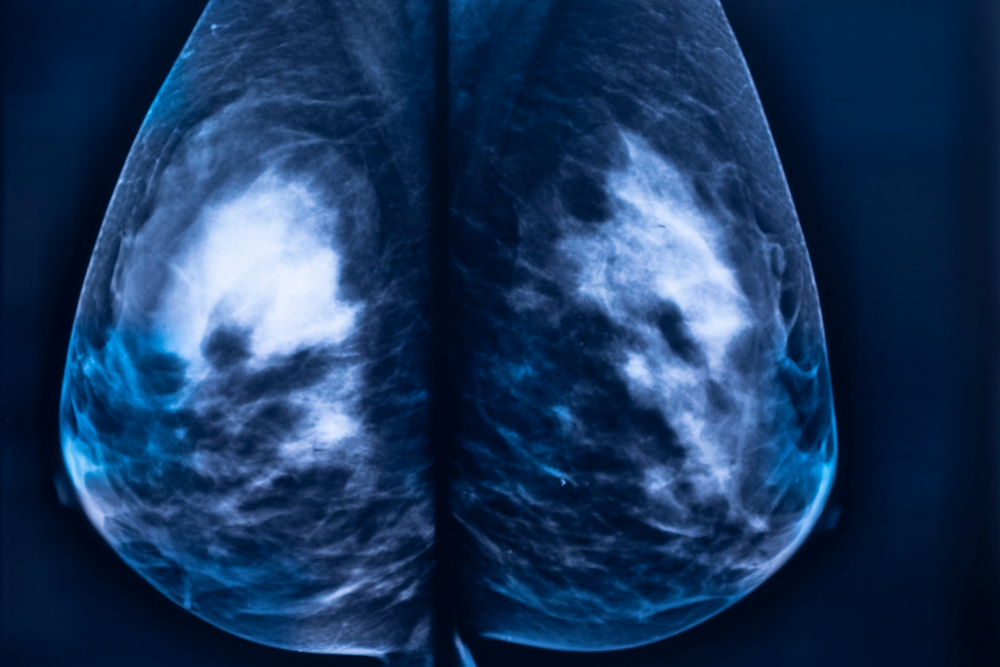

MedRay Imaging is proud to offer Full Field Digital Mammography

Screening mammograms are considered the international gold standard for detecting breast cancer early. Mammograms can usually find lumps 2 or 3 years before a woman or her primary care provider can feel them.

Diagnostic Mammograms are specialized breast x-rays. These breast x-rays are available at MedRay Imaging only and are not available at the Screening Mammography Program of British Columbia.

MedRay Imaging is proud to offer Full Field Digital Mammography. In 2013, we transitioned from film to digital, which provides improved diagnostic capabilities, less exposure, and greater image and report portability.